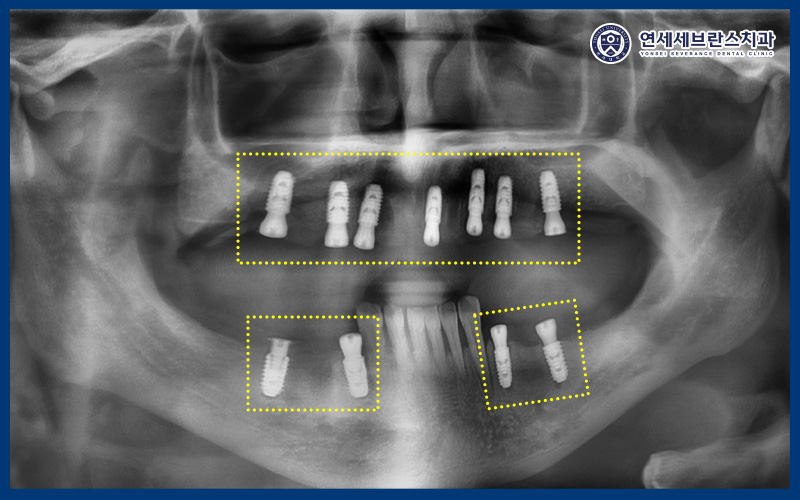

25.07.28

<위쪽 임플란트 식립>

이후 가이드를 활용하여

위쪽 먼저 임플란트

식립을 진행하였습니다.

25.08.18

<아래 임플란트 식립>

이후 아래쪽도 가이드를 사용하여

임플란트를 식립하였습니다.

이렇게 위, 아래 계획된

임플란트 식립이 완료되었답니다.